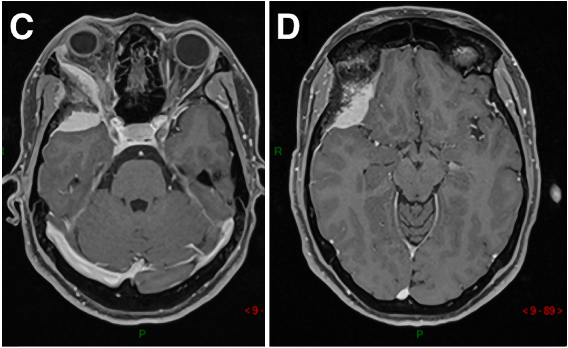

53岁男性,2012年出现V1(嗅神经)和V2(视神经)感觉减退,查出右侧Meckel’s腔脑膜瘤进行手术,术后病理结果为WHO 2级。7年后,脑膜瘤复发,再次出现严重的V1(嗅神经)、V2(视神经)和V3(动眼神经)感觉减退和疼痛。磁共振成像(MRI)显示肿瘤大面积复发,延伸至海绵窦(CS)、后颅窝(PF)、蝶窦(SS)、翼腭窝(PPF)和颞下窝(ITF)。

术前术后影像对比:肿瘤得到完全切除

术后情况:角膜炎在10天内消退,国际卫生组织II级脑膜瘤(已确诊),V3感觉减退在2个月后得到好转。